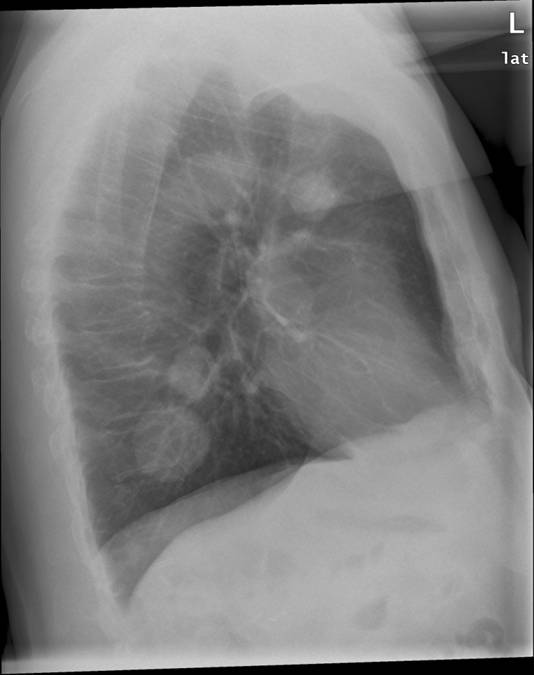

Røntgenundersøgelse af thorax som viser rundinfiltrater i begge lunger. Det skyldes kræftspredning til lungerne, såkaldte metastaser.